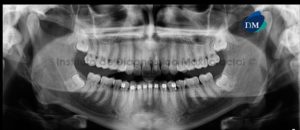

164 – Reabsorcion radicular severa